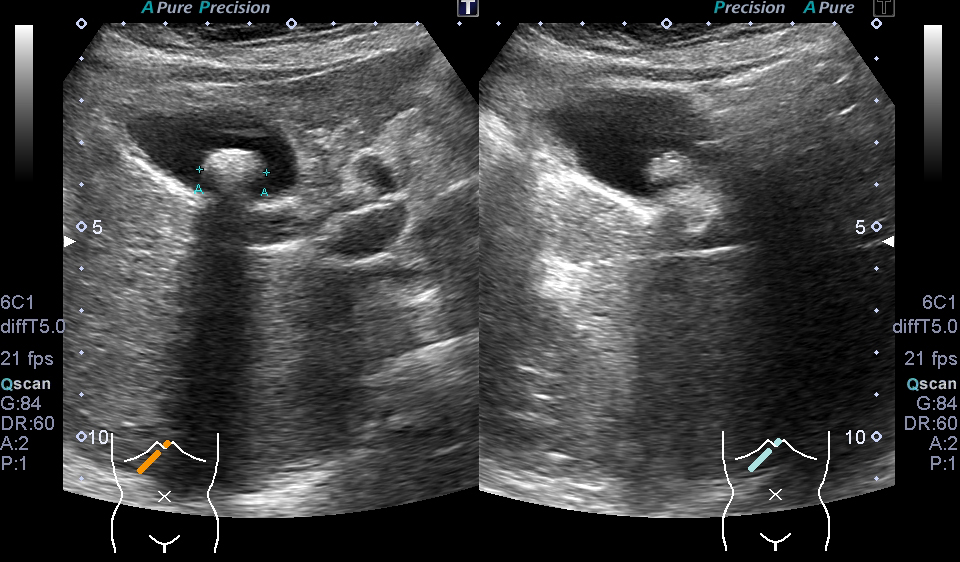

超音波(エコー) 診断画像

- 内頸動脈狭窄

- 膀胱がん

- 粉瘤

- 膝窩靭帯炎

- 乳腺症

- 乳がん

- 転移性肝がん

- 胆嚢ポリープ

- 胆石

- 大腸がん

- 前立腺肥大・前立腺がん

- 静脈瘤

- 腎細胞がん

- 子宮筋腫

- 心エコー(大動脈弁・僧帽弁閉鎖不全症)

- 鎖骨上転移

- 頸部リンパ節転移

- 胃がん

- バセドウ病